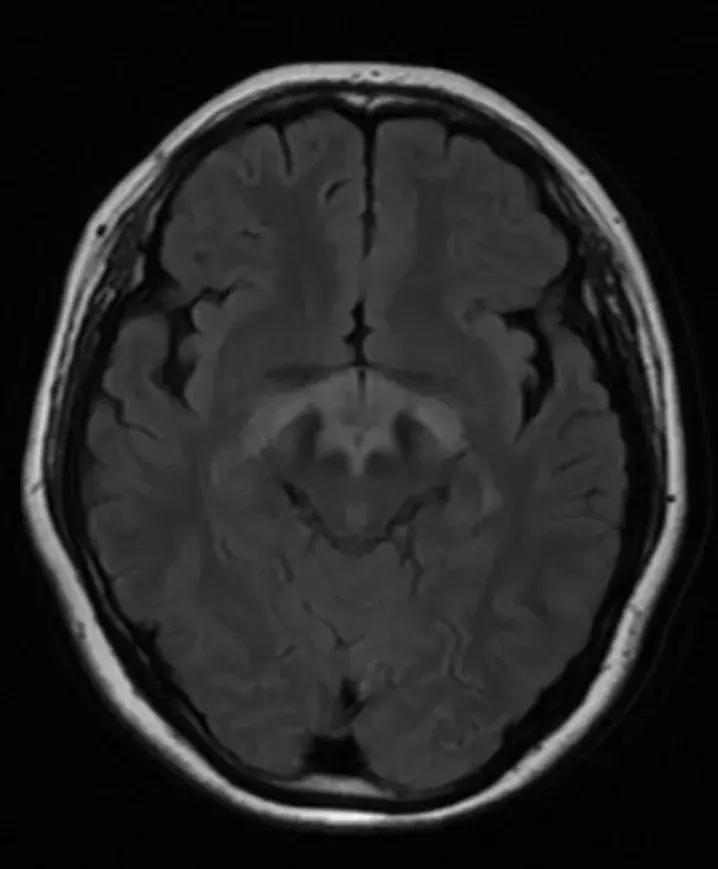

下丘脑见一类圆形异常信号灶,大小约1.6×1.4cm,T2WI呈等略高信号,T1WI呈等信号,DWI呈等信号,增强后明显异常强化,轻度压迫视交叉,FLAR见视交叉及双侧后方视束信号增高。